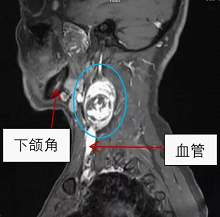

张先生和赵先生住院以后都做了颈部的磁共振检查,检查结果显示张先生的肿块长在了下颌角的边上,肿块还包绕着颈部的大血管。而赵先生的肿块是从臂丛神经上长出来的。

张先生颈部磁共振